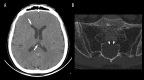

BACKGROUND The presence of fat droplets within the subarachnoid space is an uncommon finding, which is almost exclusively associated with a ruptured dermoid cyst. In a trauma setting, transthecal migration of fat droplets is an extremely rare occurrence. We present 2 case reports of intracranial transthecal migration of fatty bone marrow after sacral fractures. CASE REPORT Both patients presented to the Emergency Department (ED) after falls from a standing height. The first patient, an 84-year-old woman, suffered a stable sacral fracture extending into a large meningeal cyst within the right S2 foramen. Her initial neurological assessment and computed tomography (CT) of the head were unremarkable. As the fracture did not require surgical treatment, she was discharged home and prescribed bed rest, analgesics, and venous thromboembolism prophylaxis. Three days after the injury, she was readmitted to the ED with a mild headache, dizziness, and an episode of nausea and vomiting. A follow-up head CT revealed fat droplets in the subarachnoid space and lateral ventricles. After successful symptomatic treatment, she was discharged home in good general condition. The second patient, a 60-year-old man, underwent a head CT for a scalp hematoma, which revealed fat droplets in the 3rd ventricle and right lateral ventricle. The pelvic CT revealed a large sacral meningeal cyst with microfractures in its wall. He was discharged home on the same day and prescribed bed rest and analgesics. CONCLUSIONS The detection of intracranial intrathecal fat droplets in association with a specific trauma mechanism should initiate the search for a sacral fracture.